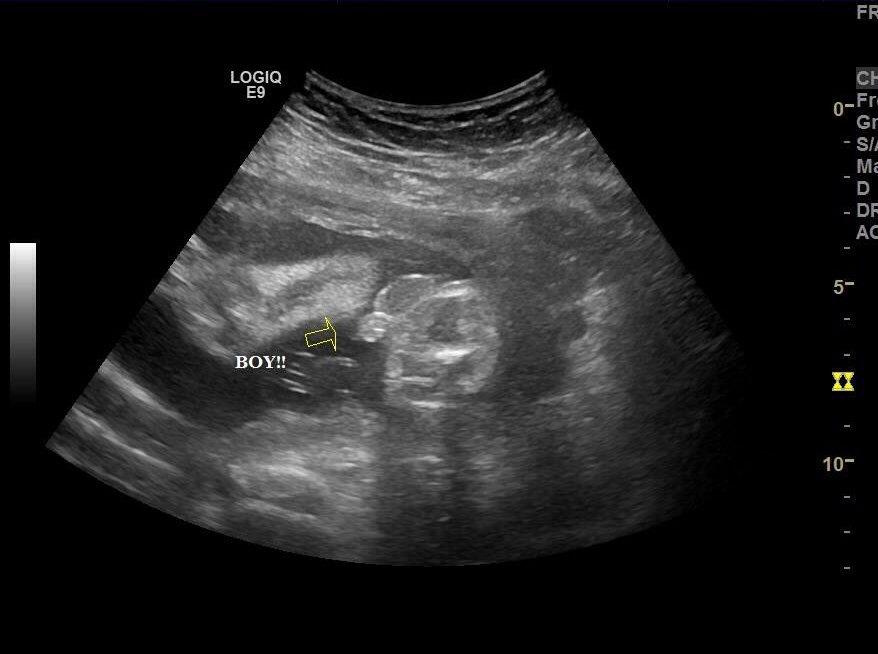

So I had a gender appt done and they told me they are 95% sure that I'm having a boy! At this point I'm super excited since I already have an 18 month old DDAttachment 23102 and bought a lot of boy cloths. Than someone is going to ruin it for me and say they could be wrong, and made me second guess the tech. I'm just nervous because I bought so many boy cloths and things so early that I won't be able to return if it is a girl. But from the picture do you guys think there's a chance this baby is a girl?

Looks like twigs & berries to me! I say BOY!